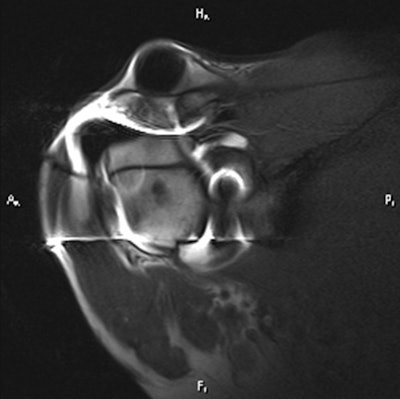

The CT image above shows a loose metallic screw (bottom arrow) and a rotator cuff tear (left arrow). The same CT below shows a second tear and loose screw (arrow). All images courtesy of Dr. Thomas Magee.

By comparison, the MR arthrogram offers virtually no details of the loose screw or rotator cuff tear.Significant findings